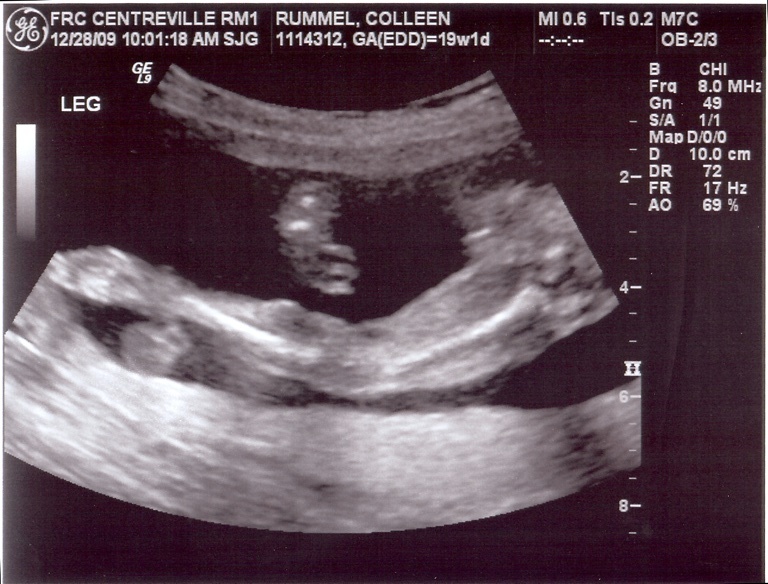

*pay no attention to the negligent mother hiding behind the computer screen*

I really and truly have been meaning to post these. But I really and truly did have an issue with my scanner. I would attempt to scan the images and it would say “uh, I’m sorry, which computer would you like these sent to?” and I’d remind it nicely that it would be for my cute little laptop. Then the scanner was all “whatever,” and wouldn’t send the images to my laptop. So I tried to dupe it by triggering the scanner remotely from my laptop (instead of the scanner itself), and I’ll be darned if the thing didn’t holler out at me “B**** please! I can see you in there!” and wouldn’t send me the images. So I was forced to ask Justin a few times to scan the sonogram images for me. I think I literally heard the scanner purr “oh, the Apple wants some images scanned? Sure! Whatever you want, sweetie!”